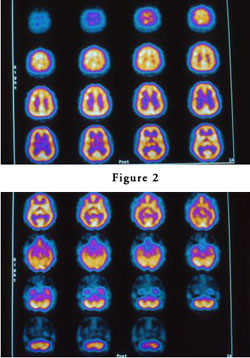

Să vedem în continuare cum apar și se manifestă din punct de vedere neurologic stările superioare de conştiinţă. Ele sunt rezultatul diminuării, al estompării percepției obişnuite a eului (de fapt, a egoului, AHAMKARA) şi creează senzaţia euforică de absorbţie într-o realitate mai vastă. Cercetătorii americani, studiind scanările SPECT (Single Photon Emission Computed Tomography) ale creierului în timpul stărilor profunde de meditaţie, au observat că aceste senzaţii se produc în legătură cu modificarea activităţii ariei cerebrale care integrează simţul orientării (aria corticală asociată cu orientarea în spațiu). Mai exact, aceasta apare datorită privării ei de stimulii neurali. Această arie corticală este situată în secţiunea posterioară a lobului parietal şi ea primeşte stimuli senzoriali de la simţul tactil şi de la celelalte simţuri, în special simțul văzului şi simțul auzului.

Ea îi oferă omului capacitatea de a crea senzaţia de tridimensionalitate a trupului şi de orientare a acestuia în spaţiu. Există două arii cerebrale care integrează simţul orientării, localizate în fiecare emisferă cerebrală, care realizează operaţii distincte, dar corelate, aşa cum de altfel s-a putut vizualiza în imaginile SPECT. Aria corticală care integrează simțul orientării în spațiu din emisfera cerebrală dreaptă este răspunzătoare pentru crearea matricei neurale, care este conexă cu experiența spaţiului fizic, iar cea din emisfera cerebrală stângă joacă un rol foarte important în generarea percepției ce este corelată cu starea de eu subiectiv.